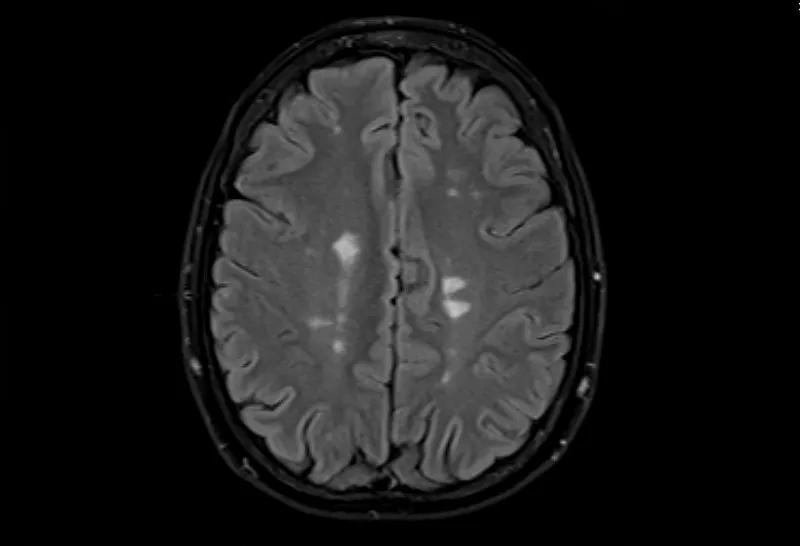

• 大腦的MRI掃描可以顯示損傷區(qū)域,但沒有單一的測(cè)試可以診斷MS。

多發(fā)性腦硬化癥的磁共振成像,軸位Flair視圖

測(cè)試的組合用于診斷MS。最好的測(cè)試是對(duì)您的大腦和脊髓進(jìn)行核磁共振檢查,以檢測(cè)損傷區(qū)域。您可能還需要進(jìn)行血液檢查、腰椎穿刺和測(cè)量神經(jīng)活動(dòng)的測(cè)試。